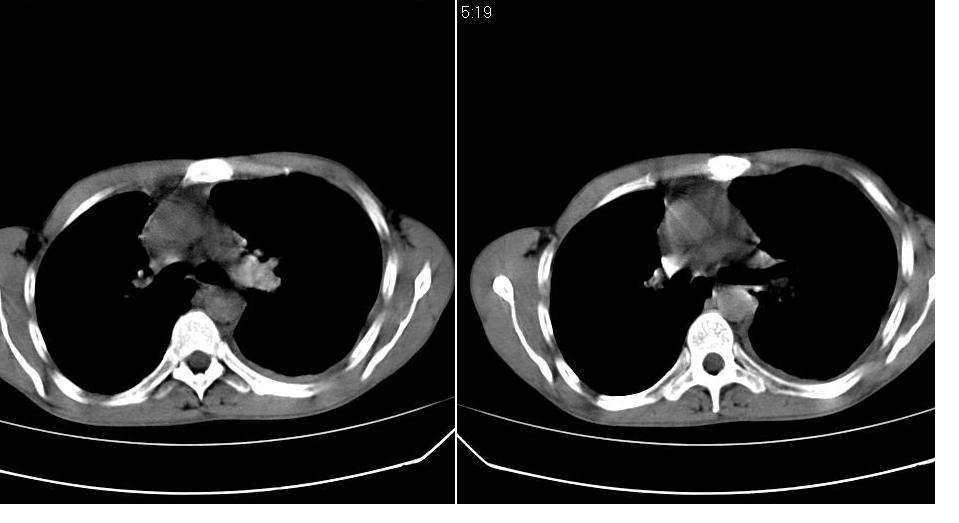

以下是引用苯小孩在2007-6-27 15:09:00的发言:[br]考虑:1、右肺继发性肺结核.2、双侧包裹性积液<胸腔及叶间>3、双侧局部胸膜增厚.[br]建议胸水化验检查.

以下是引用yanghaochen88在2007-6-27 15:08:00的发言:[br]双肺上野散在粟粒状影、包裹性积液、胸膜增厚粘连、叶间积液---tb,至于分型还得结合病史体征细究妥当些。

以下是引用zjzjr在2007-6-27 16:49:00的发言:[br]肺结核、结核性胸膜炎。